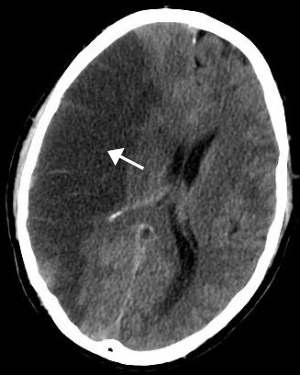

뇌졸중 전조증상 체크리스트

뇌졸중은 신속한 대응이 중요한 질환입니다. 전조증상을 빠르게 인식하고 즉각적인 조치를 취하는 것이 생명을 구하고 후유증을 최소화하는 데 중요한 역할을 합니다.

뇌졸중의 전조증상을 체크리스트 형태로 정리하여, 누구나 쉽게 확인하고 대처할 수 있도록 도와드리겠습니다.